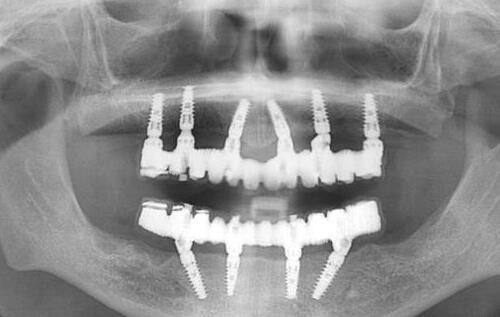

广州曙光口腔医院的口碑蛮好的,特别多患者都对其赞不绝口。大家都夸广州曙光口腔种植牙收费不贵技术靠谱。在种植牙方面,医院不仅价格合理,而且医生的技术水平也特别高。医生们经过专精的培训和丰富的临床实践,能够熟练地开展各种种植牙手术,为患者提供高质量的种植牙服务。

| 种植牙 | 1380起一颗 |

除了上述常见的口腔项目,广州曙光口腔医院还有一些特色的收费项目。比如穿翼板种植牙,价格为4999元一颗。穿翼板种植牙是一种比较精良的种植牙技术,对于一些牙槽骨条件较差的患者来说,是一种良好的解决方案。而凸嘴矫正,价格为5899元,能够帮助那些有凸嘴问题的患者改善面部美观。